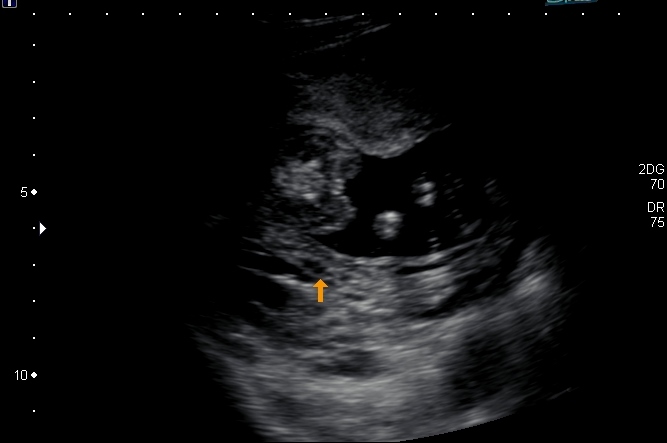

Tech said we are expecting a girl! But then when i got home and saw the pics I can't quite make out what she's pointing to ...

The three little lines between the two humps (the legs) this is a very girl shot congratulations!!!!